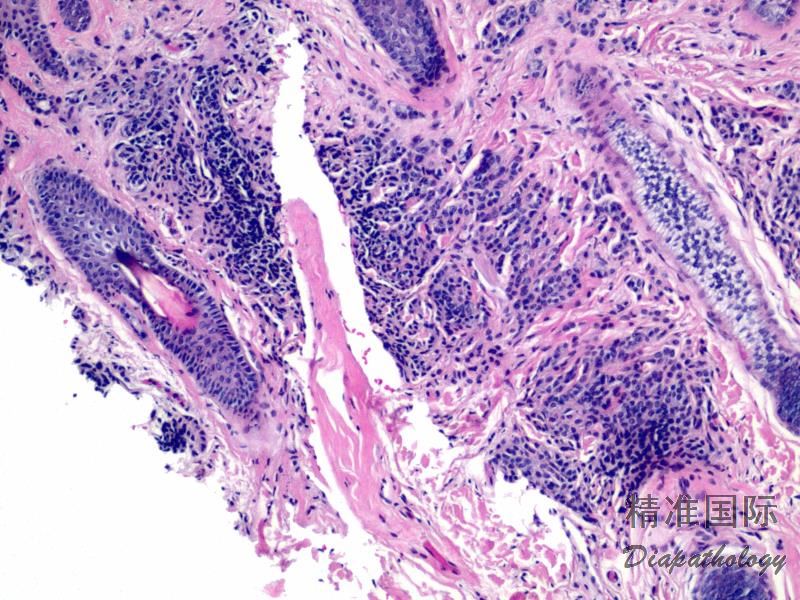

生长方式

原位黑色素瘤伴异型黑色素细胞真皮浸润,无分化成熟;

典型病例表皮-真皮交界处细胞生长活跃使得表皮-真皮分界模糊,单个或成簇细胞 Paget 样表皮内扩展;

假腺样、假乳头状、栅栏状、编织状、血管外皮瘤样、梁状、spitz 痣样、疣状、痣样、围绕血管生长等

间质:促结缔组织增生、胶原化、黏液、骨化、软骨、破骨巨细胞样反应、淋巴细胞结节、色素沉积、吞噬色素色巨噬细胞聚集、血管瘤样增生;

与周围组织关系:

吞噬上皮脚,上皮脚消失,上皮变薄;

浸润皮下脂肪、横纹肌、血管、神经等;